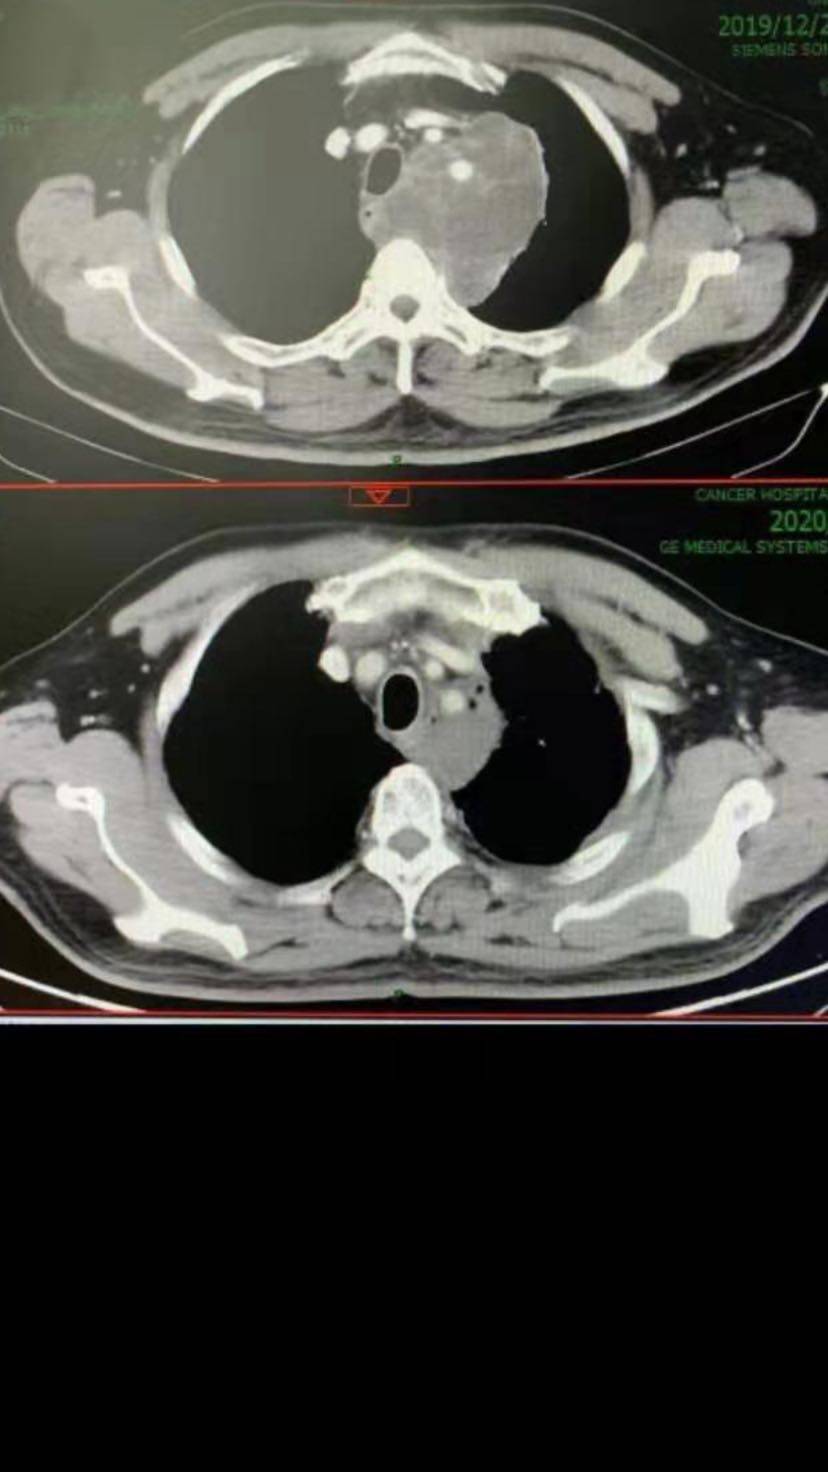

效果显著